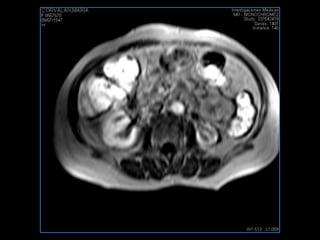

PROTOCOLO abdomen COR T2, AXIAL supresion grasa AX T1 +SAG T2  CON   GADOLINIO :  COR T1+AX T1(DIN) SAT: NO  FASE: RL THK: 6MM  COIL:  GAP: (FACTOR 1.4) 2MM FOV: 40 CM NEX:2 SINCRONIZACION RESPIRATORIA EN 3 O 4 CICLOS ALE

PROTOCOLO pancreas/ riñon AXIAL fat sat /AX in phase out phase AX T1 +SAG T2  COR T2, CON   GADOLINIO :  COR T1+AX T1(DIN) SAT: NO  FASE: RL THK: 4MM  COIL:  GAP: (FACTOR 1.4) 1MM FOV: 40 CM NEX:2 SINCRONIZACION RESPIRATORIA EN 3 O 4 CICLOS ALE